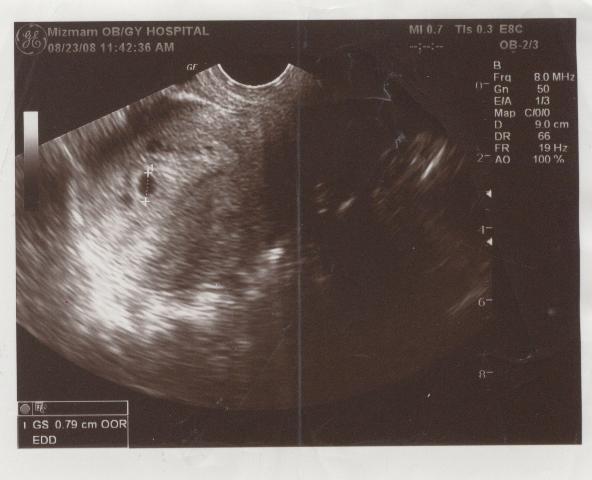

우리 아기 별 - 초음파사진01-5주.jpg

첫째 아이 초음파 사진